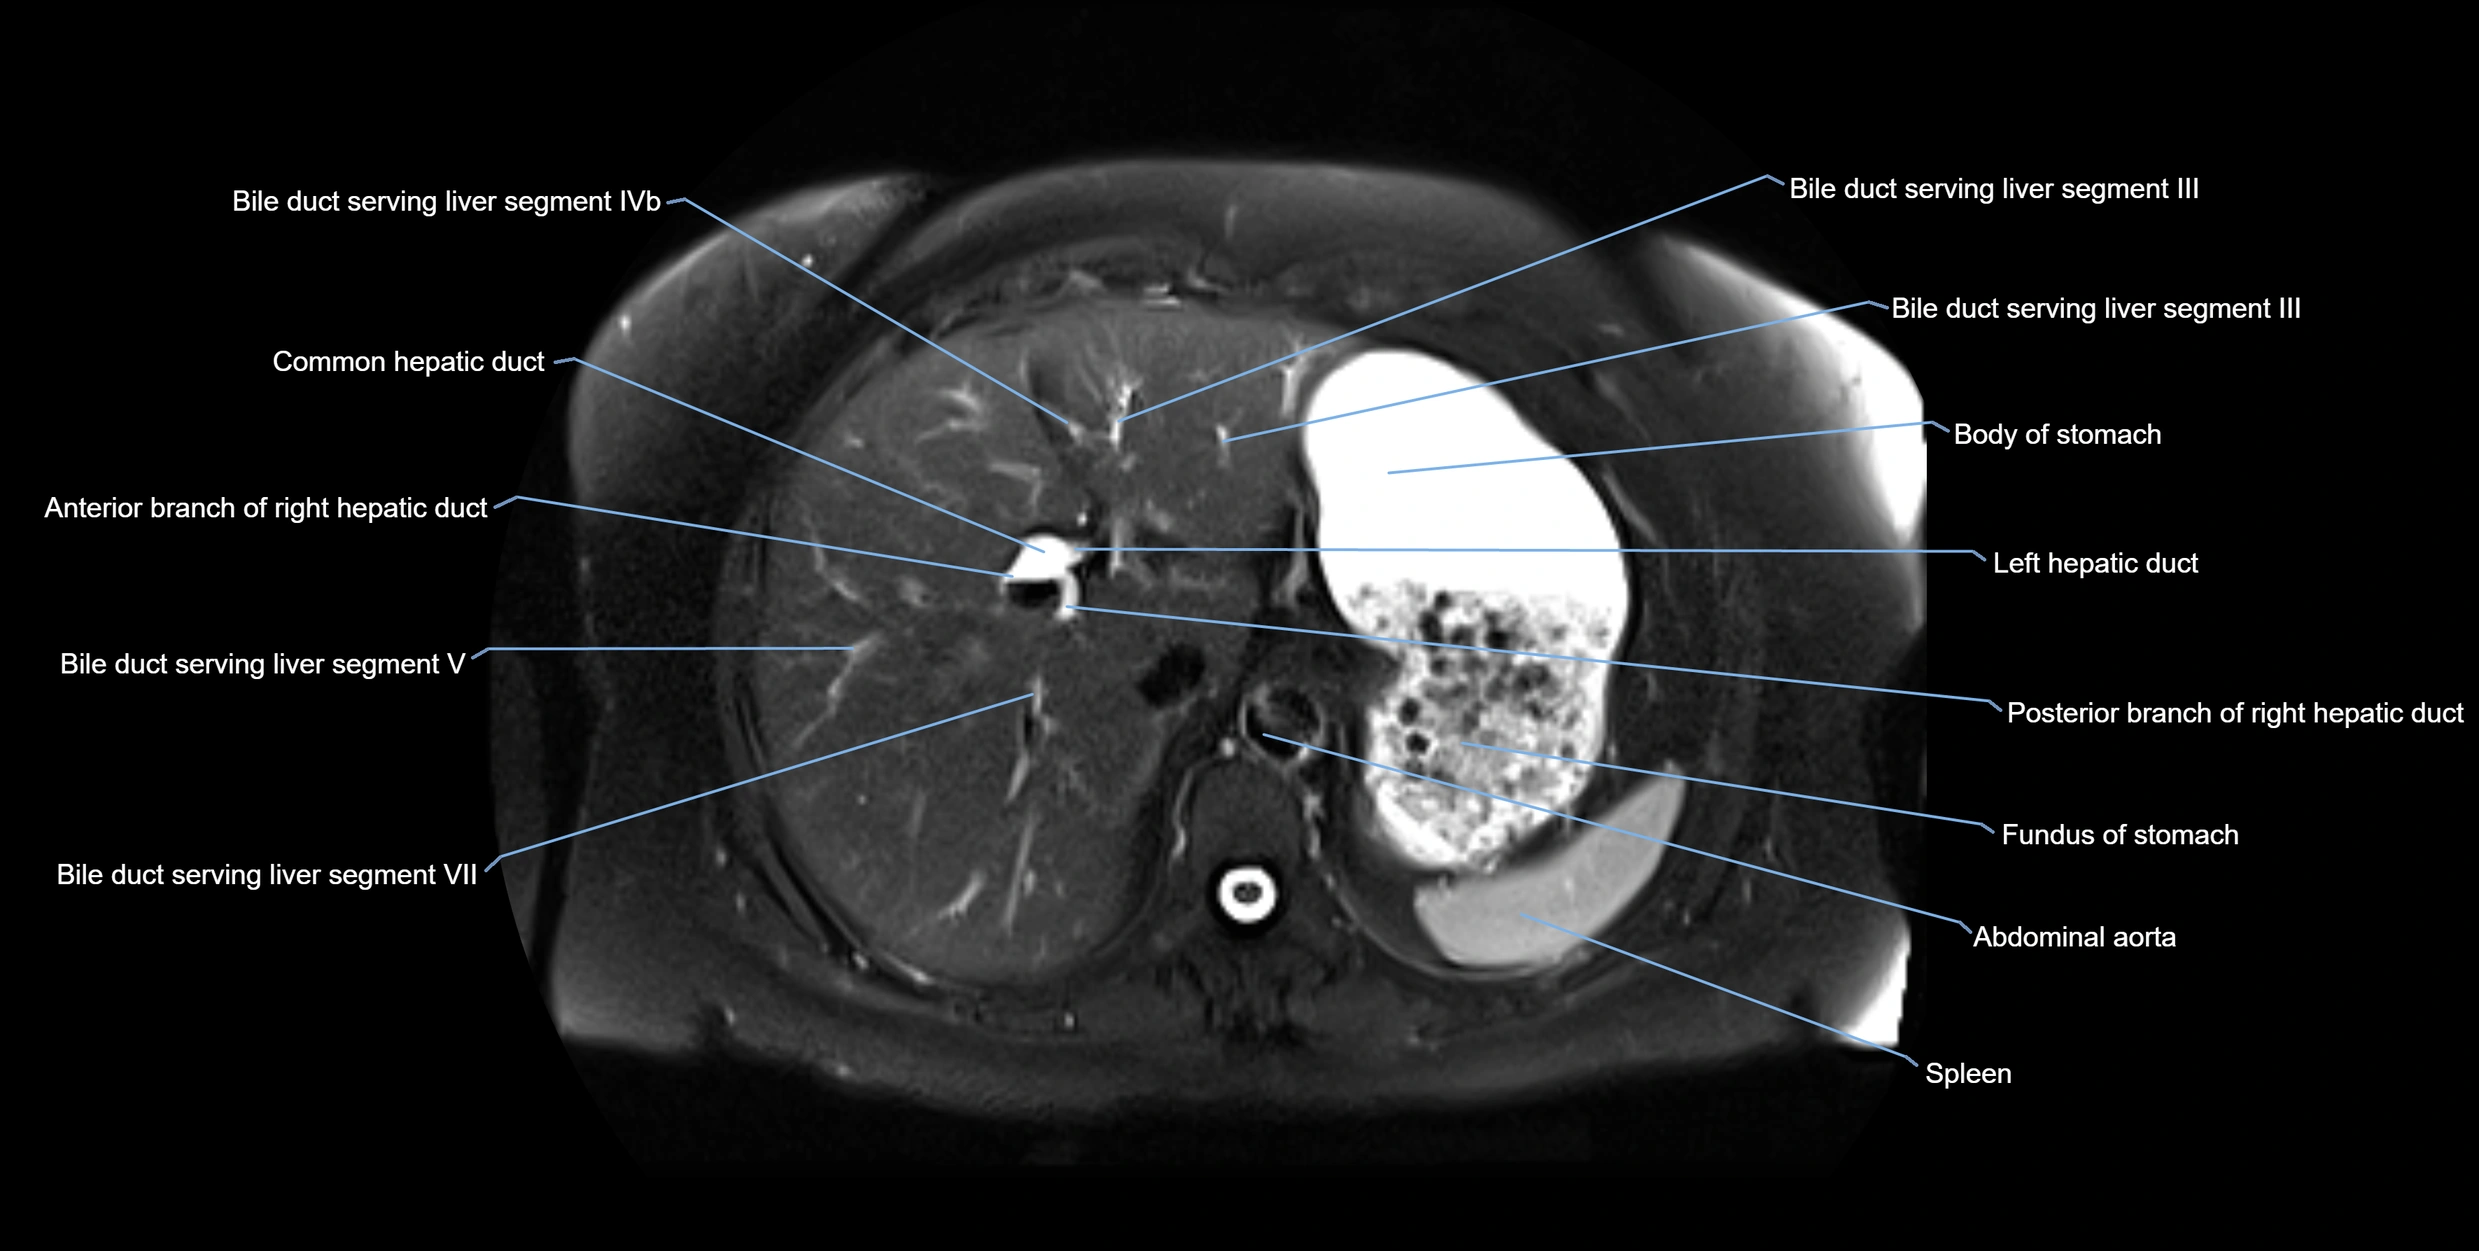

MRI image

image